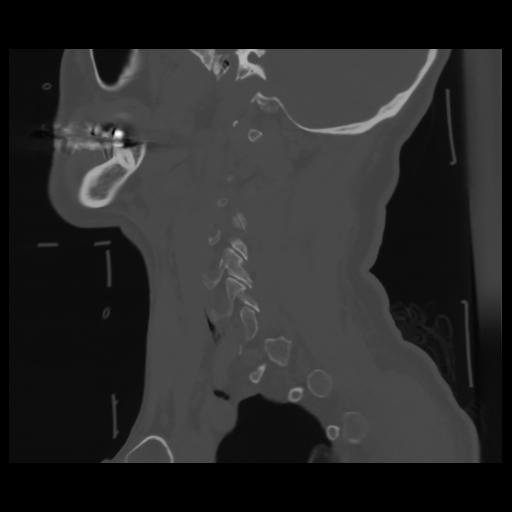

14 P.BLANDAS,,Sagittal,2.000,P.BLANDAS,Sagittal,